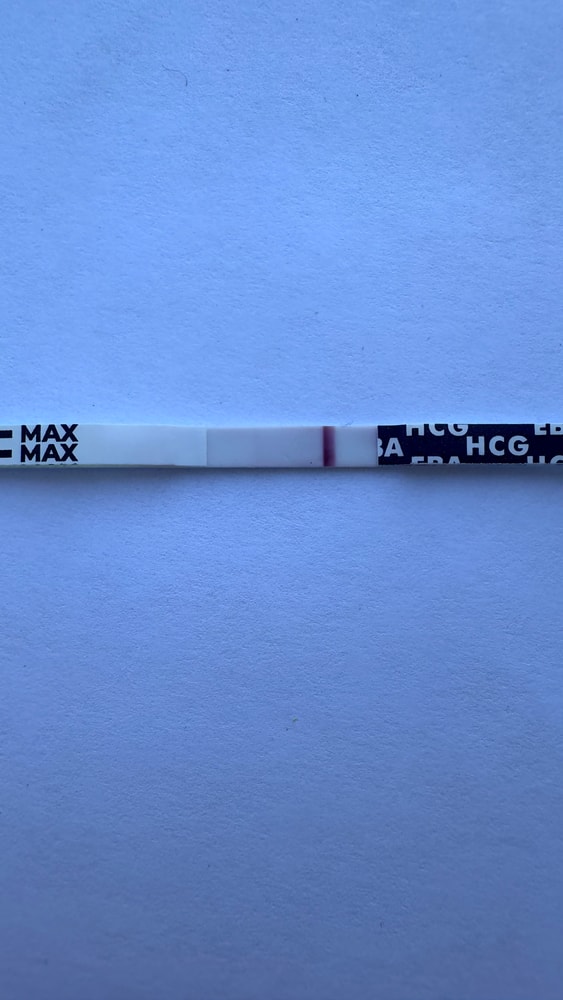

Тесты в студию🤗

Вот и мне отреагентили эти прекрасные тесты.

Нееет, ну за 5 лет, с таким я еще не сталкивалась!